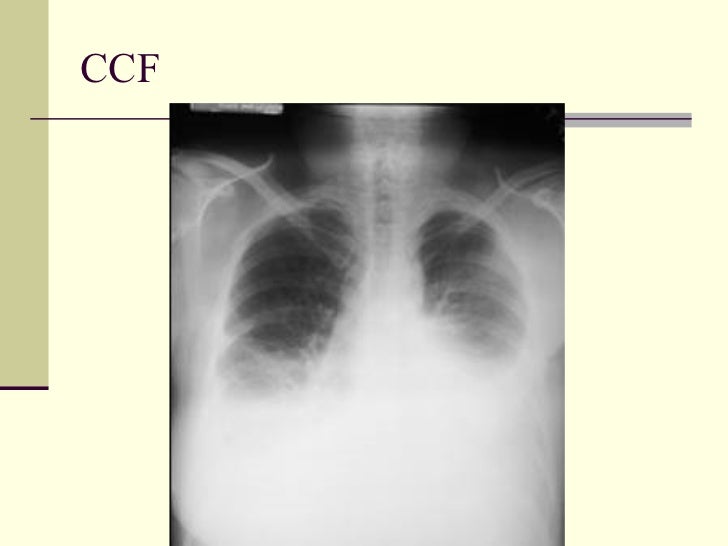

68. 76. CCF

67. 75. Pleural Effusion 1. CHF 2. Mets 3. Pancreatitis 4. Pulmonary embolism 5. Trauma 6. Empyema 7. Collagen vascular 8. Ovarian tumor (Meig’s Syndrome) 9. Chylothorax